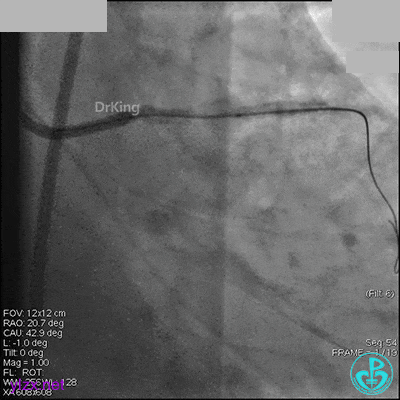

1周后再次上台,右冠脉3级血流,3段局限性严重狭窄,内膜模糊,应该是上次操作夹层遗留下的血肿。

先处理前降支开口严重狭窄并顺利植入前降支到左主干支架。